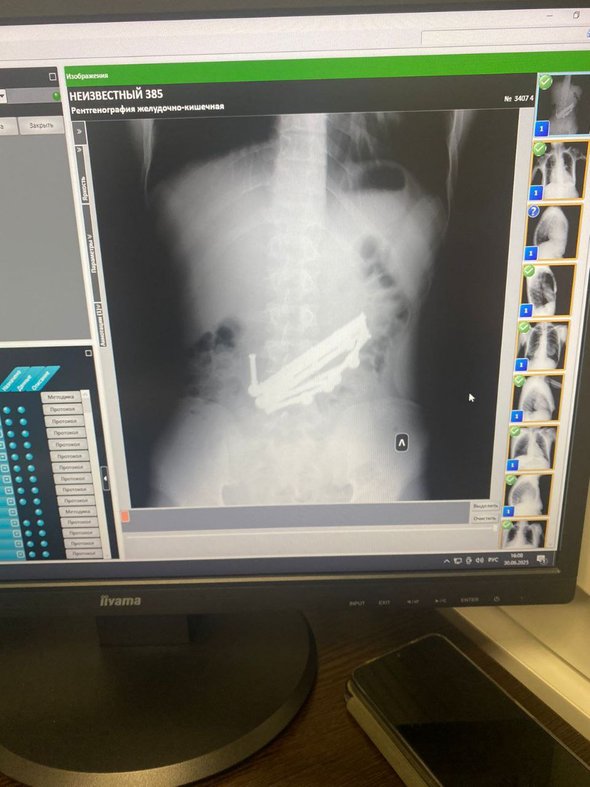

В приемное отделение Владивостокской клинической больницы № 4 доставили 18-летнего молодого человека с жалобами на дискомфорт и тяжесть в животе. В больнице рентген показал наличие объемных инородных предметов в желудке и тонком кишечнике.

Хирурги экстренно прооперировали молодого человека. На протяжении двух часов врачи аккуратно и кропотливо извлекали звенья непростой округлой формы, которые было нелегко подцепить медицинскими инструментами. Всего было извлечено 420 г деталей магнитного конструктора в форме шариков и коротких трубок.